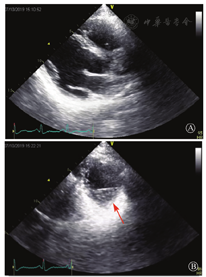

患者男性,20岁,主因"胸痛4个月,加重1月余"于2019年7月10日入院。患者2019年4月无明显诱因出现心前区隐痛,VAS 3分,无放射,无胸闷、憋气、活动后气短,每月发作1~2次,未在意。同年5月体检发现,肌酸激酶(CK)2 928 U/L、肌酸激酶MB质量(CK-MB)46 U/L、心肌肌钙蛋白I(cTnI)0.055 ng/ml。6月初,患者"感冒"后出现心前区疼痛加重,为过电样疼痛,VAS 5分,无放射,持续约30~60 min可好转,胸痛每周约发作2次,否认呼吸困难、胸闷、心悸,否认活动耐量下降。6月8日,患者就诊于外院查血生化:CK 1 215→1 433 U/L,CK-MB 47 U/L,cTnI 30.17→31.79 ng/L;血脂(-);抗核抗体谱(-);超声心动图:左室增大,左室舒张末内径57 mm,左室射血分数39%,轻度二尖瓣关闭不全;磁共振心肌灌注延迟动态成像(图1):左室稍增大,收缩功能稍减低;基底部至心尖部左室下壁及侧壁、心尖部左室前壁心外膜下心肌纤维化,考虑非缺血性心肌病;肌电图:肌源性损害(偏慢性)。诊断"多发性肌炎、心肌损伤",予患者倍他乐克缓释片23.75 mg/d、培哚普利0.5 mg/d、螺内酯20 mg/d口服,患者未再出现心前区疼痛,但步行1 km左右会出现气短、乏力。为进一步明确心力衰竭病因收入我院。患者上高中起出现体育课等剧烈活动后双下肢明显乏力,不能耐受1 km长跑类运动,日常体力活动不受影响,否认肌肉酸痛等不适。此次发病以来,一般情况尚可,否认尿量减少,体重无明显变化。既往史:否认高血压、冠心病、糖尿病病史。个人史:否认特殊毒物药物接触史,无烟酒嗜好。婚育史、家族史:未婚未育,否认家族类似病史,否认遗传病史。入院查体:脉搏69次/min,血压112/70 mmHg,指氧(自然状态)98%,体质指数21.1 kg/m2;无皮疹;双肺呼吸音清;心律齐,未闻及杂音;肝脾不大;双侧腓肠肌肥大,肌肉无压痛;四肢肌力Ⅴ级、肌张力正常。双下肢不肿。辅助检查:入室床旁超声心动图提示左室壁运动普遍减低,心尖部、左室下后壁为著,肌小梁增多。

左室壁较广泛心外膜下延迟强化,可见左室下后壁肌小梁增多(箭头所示)